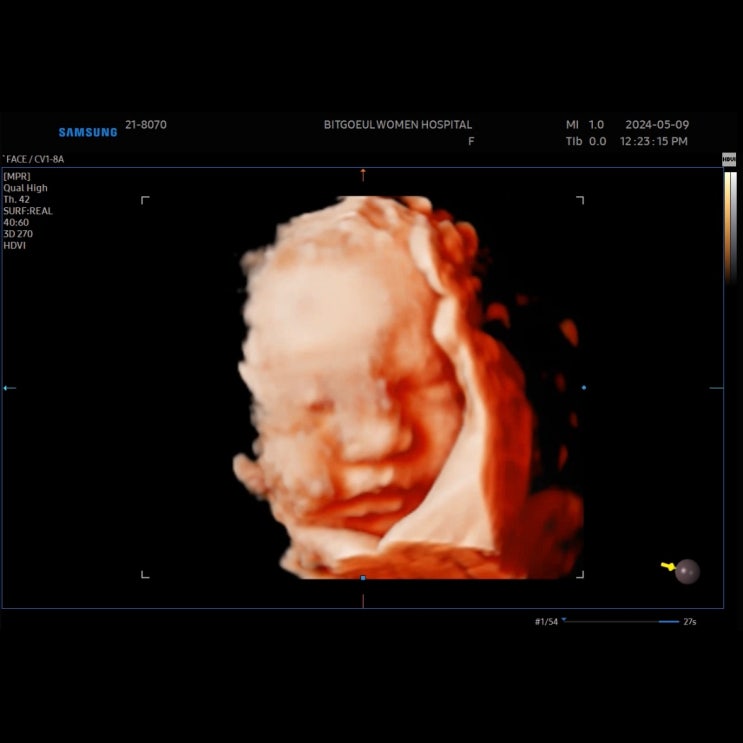

임신 35주차) 빛고을 여성병원 정기검진- 태동검사, 입체초음파, 분만 방법

임신 35주차) 빛고을 여성병원 정기검진 태동검사, 입체초음파, 분만방법 @드리미 어느새 D-31일! 35주차 ...